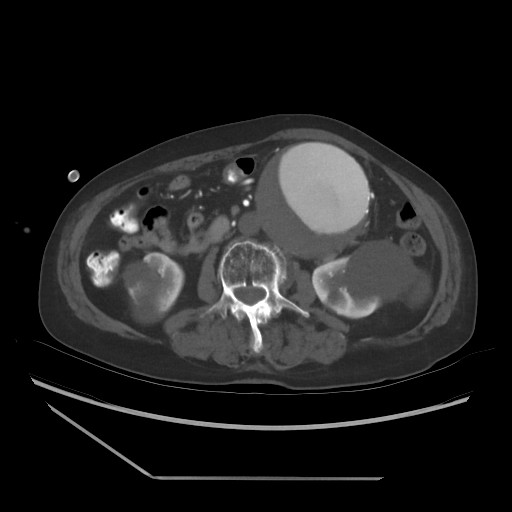

(AAA) diagnosis CT.jpg

The aneurysm is typically diagnosed when the diameter exceeds 3 centimeters or is more than 50% larger than the normal aorta. Diagnosis is primarily done through imaging techniques like ultrasound, CT scan, or MRI, especially during screening for high-risk groups.